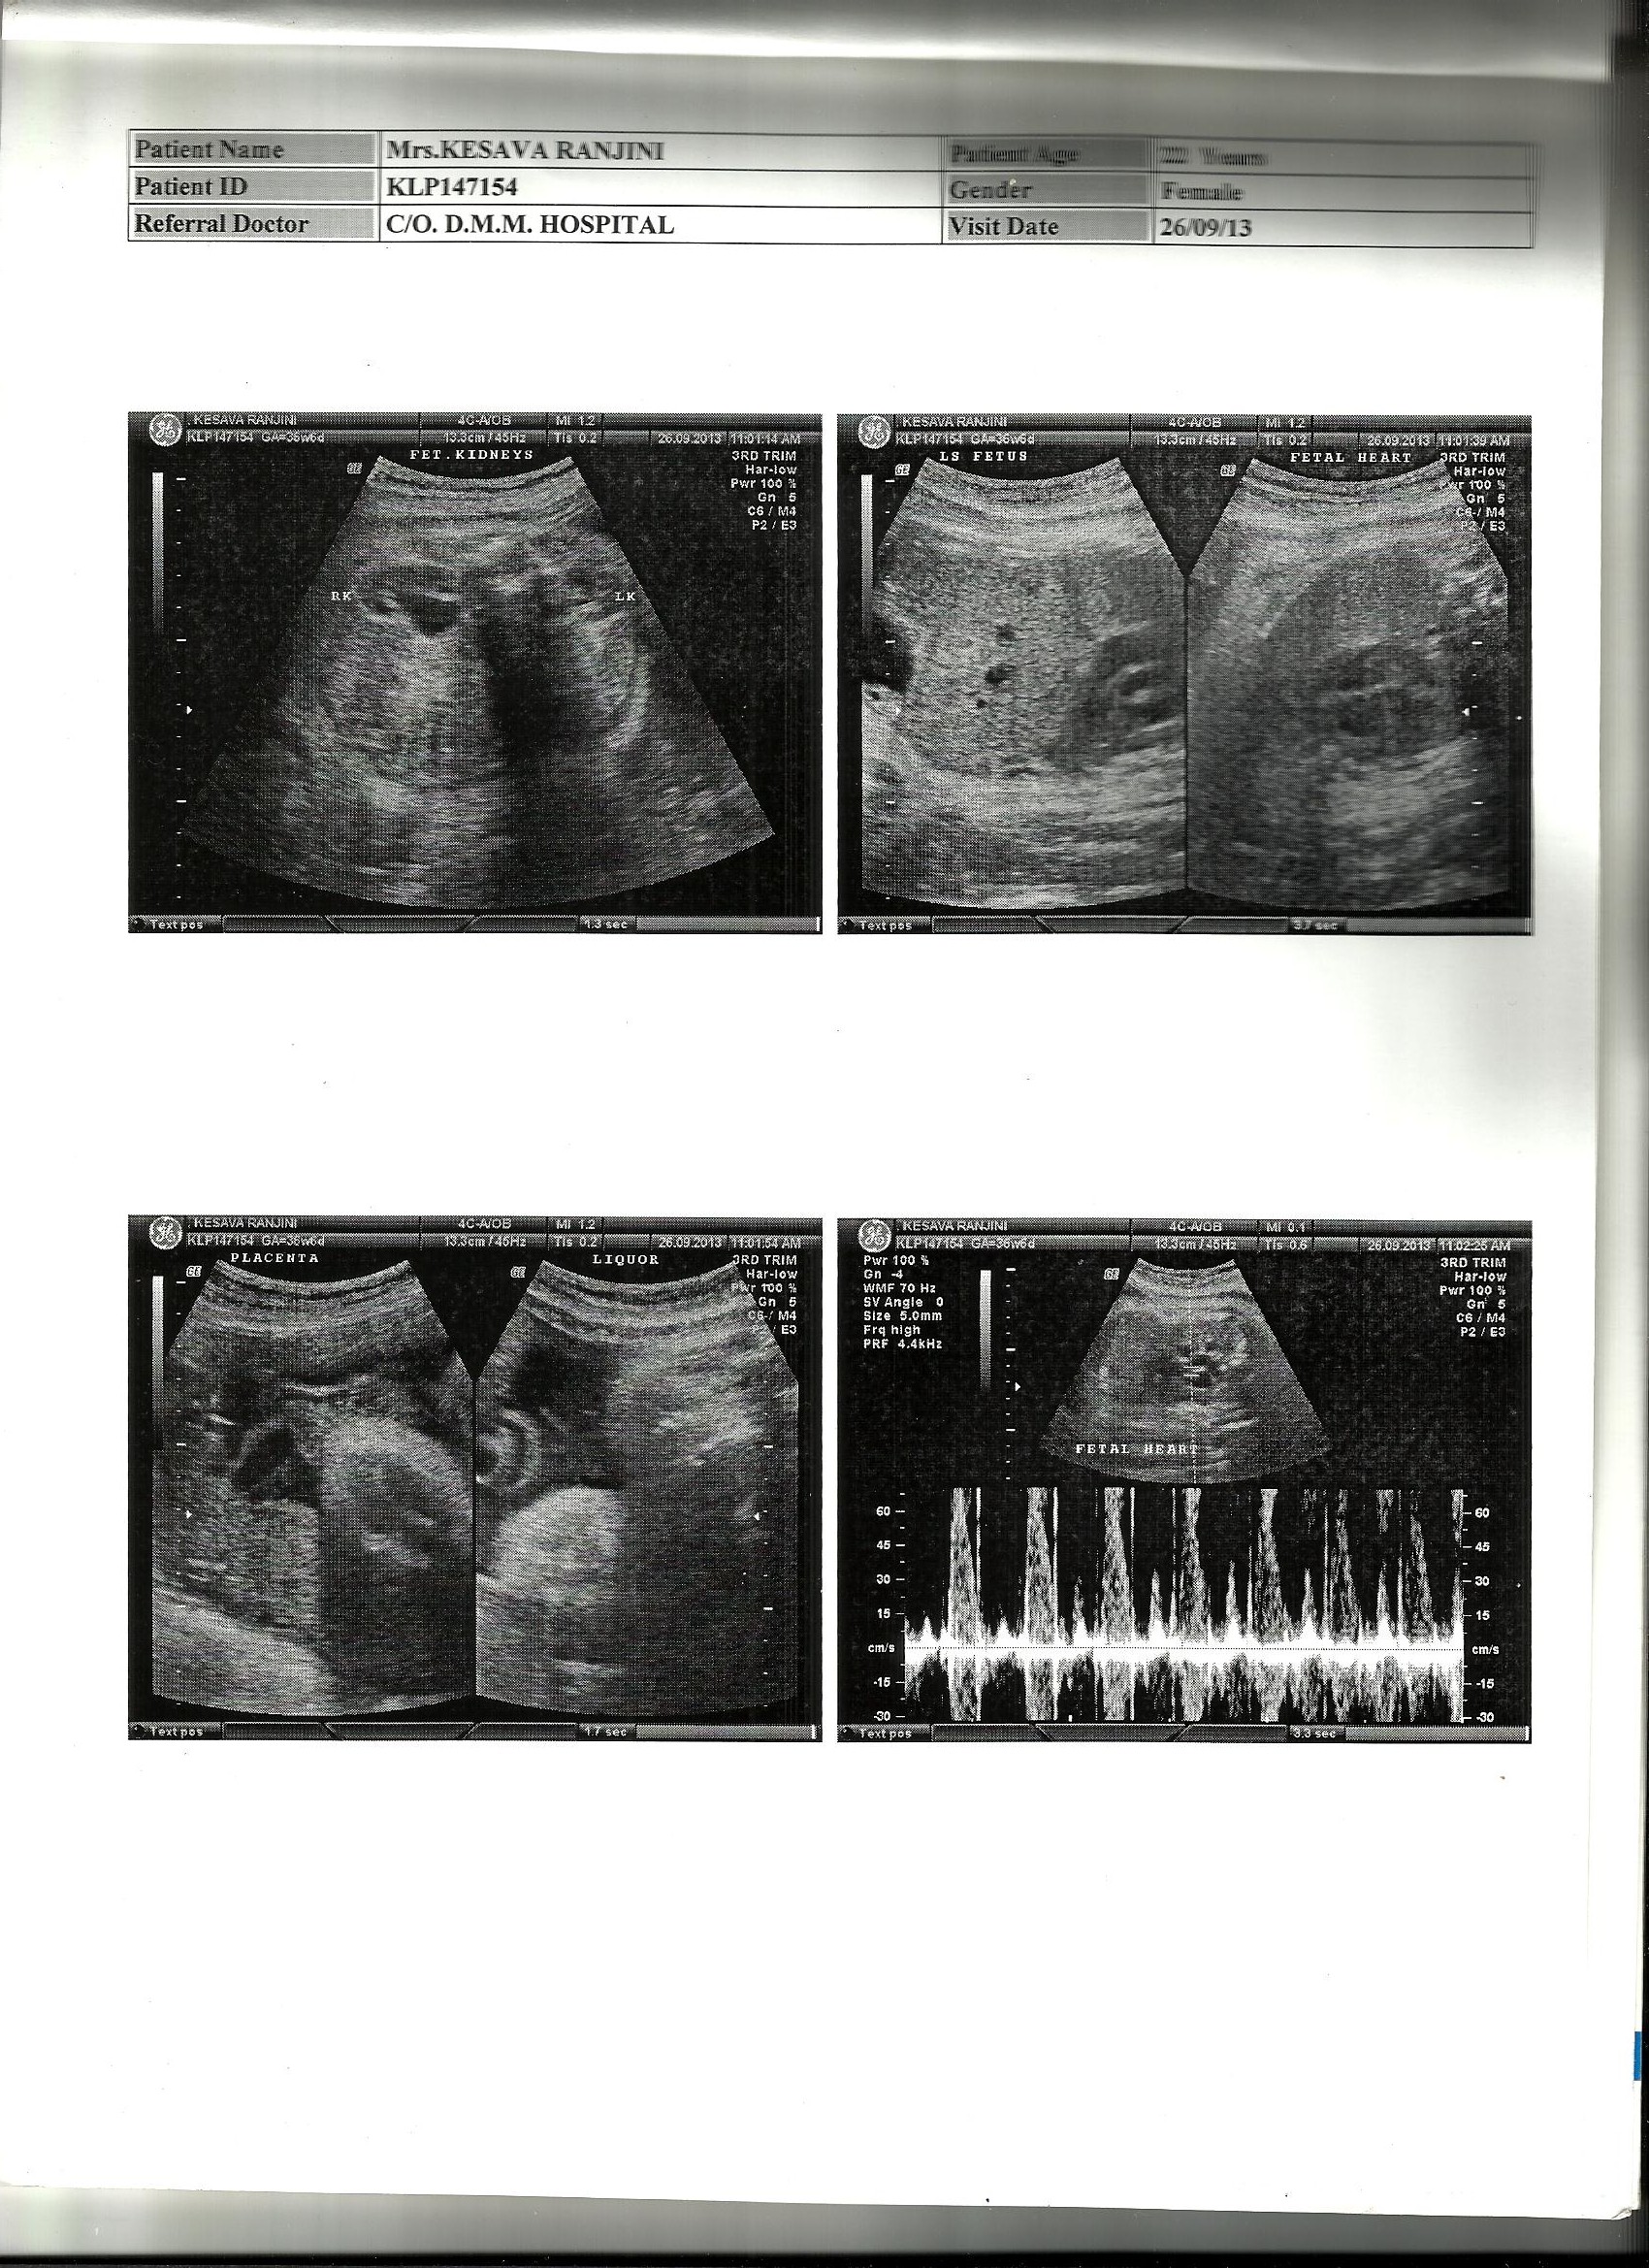

Yesterday the ninth month scan results came up!! posting the same for your guesses!!! Please post your guesses. Oct 18th is the due date. Feeling Excited!!!Attachment 14422Attachment 14423